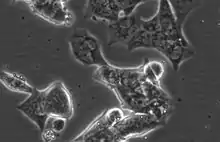

Representative phase-contrast image of LAPC4 cells. 32X magnification.

LAPC4 are a lowly adherent, epithelial cell line with high Androgen receptor and Prostate specific antigen expression.[4] Unlike the other commonly utilized, Androgen receptor positive prostate cancer cell lines LNCaP and VCaP, LAPC4 have high expression of Keratin 5, a basal marker, as well as the luminal markers Keratin 8 and Keratin 18.[4] LAPC4 also expresses mutated P53 (R175H). [4]